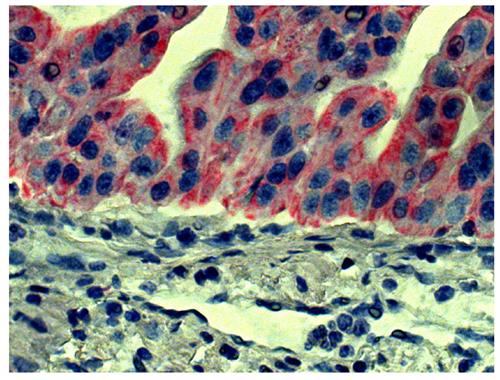

ARG23804 Goat anti-Mouse IgG2a antibody (AP), pre-adsorbed IHC-P image

Immunohistochemistry: Paraffin-embedded Human gastric cancer tissue was stained with Mouse anti-Human CD44 followed by ARG23804 Goat anti-Mouse IgG2a antibody (AP), pre-adsorbed, Red AP, hematoxylin, and mounted with Fluoromount-G.